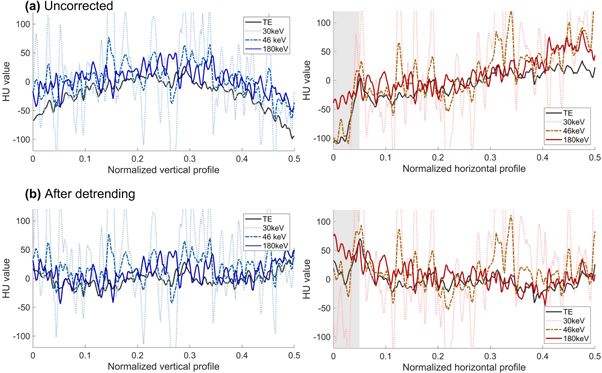

The cupping artefact was not mitigated when the virtual monoenergy was increased (figure 5(a)). Detrending reduced cupping for all monoenergies and TE reconstructions (figure 5(b)).

Figure 5. Left: Horizontal profiles of different virtual monenergies over the homogeneous region. Right: Vertical profiles of different virtual monoenergies over the homogeneous region. The spikes showing in the 30 keV and 46 keV images are caused by ringing artefacts. The grey region highlights the beam hardening area of the image.